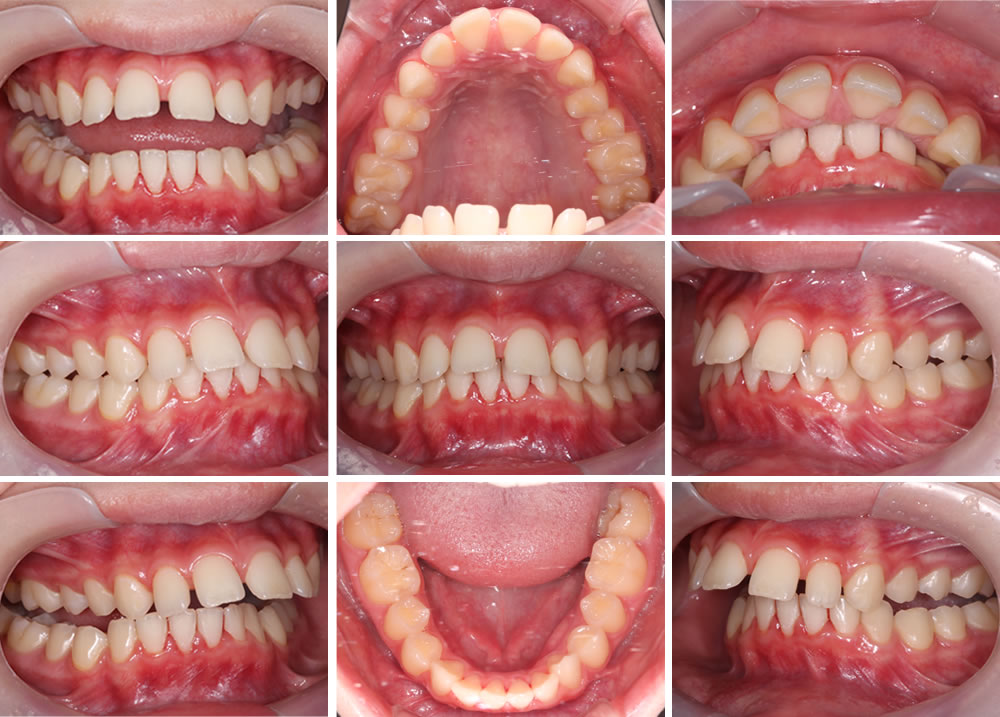

こちらの患者さまは、前歯の前突感が気になるとの主訴で来院されました。

初診時の口腔内写真です。上顎の前歯が前に出ていて、隙間が空いていることがわかります。下の歯並びはおおむね綺麗ですが、奥歯の噛み合わせが逆になっている部分もあり、こちらも矯正していくことにしました。